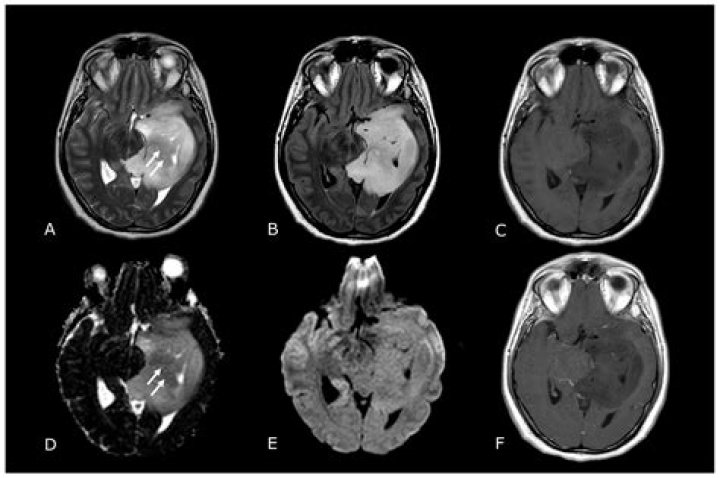

What is a butterfly tumor?

Butterfly glioblastoma (bGBM) is a malignant glioma that crosses the corpus callous with bilateral cerebral hemisphere involvement. Literature reports are scarce and highlight a dismal prognosis with limited successful treatment options.